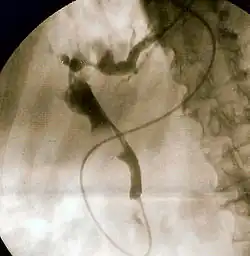

The gold standard test for biliary obstruction is still endoscopic retrograde cholangiopancreatography (ERCP). This involves the use of endoscopy (passing a tube through the mouth into the esophagus, stomach and thence to the duodenum) to pass a small cannula into the bile duct. At that point, radiocontrast is injected to opacify the duct, and X-rays are taken to get a visual impression of the biliary system. On the endoscopic image of the ampulla, one can sometimes see a protuberant ampulla from an impacted gallstone in the common bile duct or the frank extrusion of pus from the common bile duct orifice. On the X-ray images (known as cholangiograms), gallstones are visible as non-opacified areas in the contour of the duct. For diagnostic purposes, ERCP has now generally been replaced by MRCP. ERCP is only used first-line in critically ill patients in whom delay for diagnostic tests is not acceptable; however, if the index of suspicion for cholangitis is high, an ERCP is typically done to achieve drainage of the obstructed common bile duct.[1]